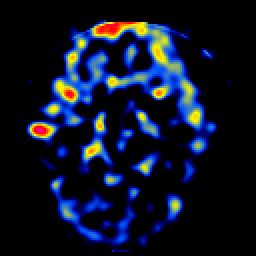

SPECT TL Study #5 -- Slice #24

[Home][Help][Clinical][Tour 1][Tour 2][Tour 3] Slice 24